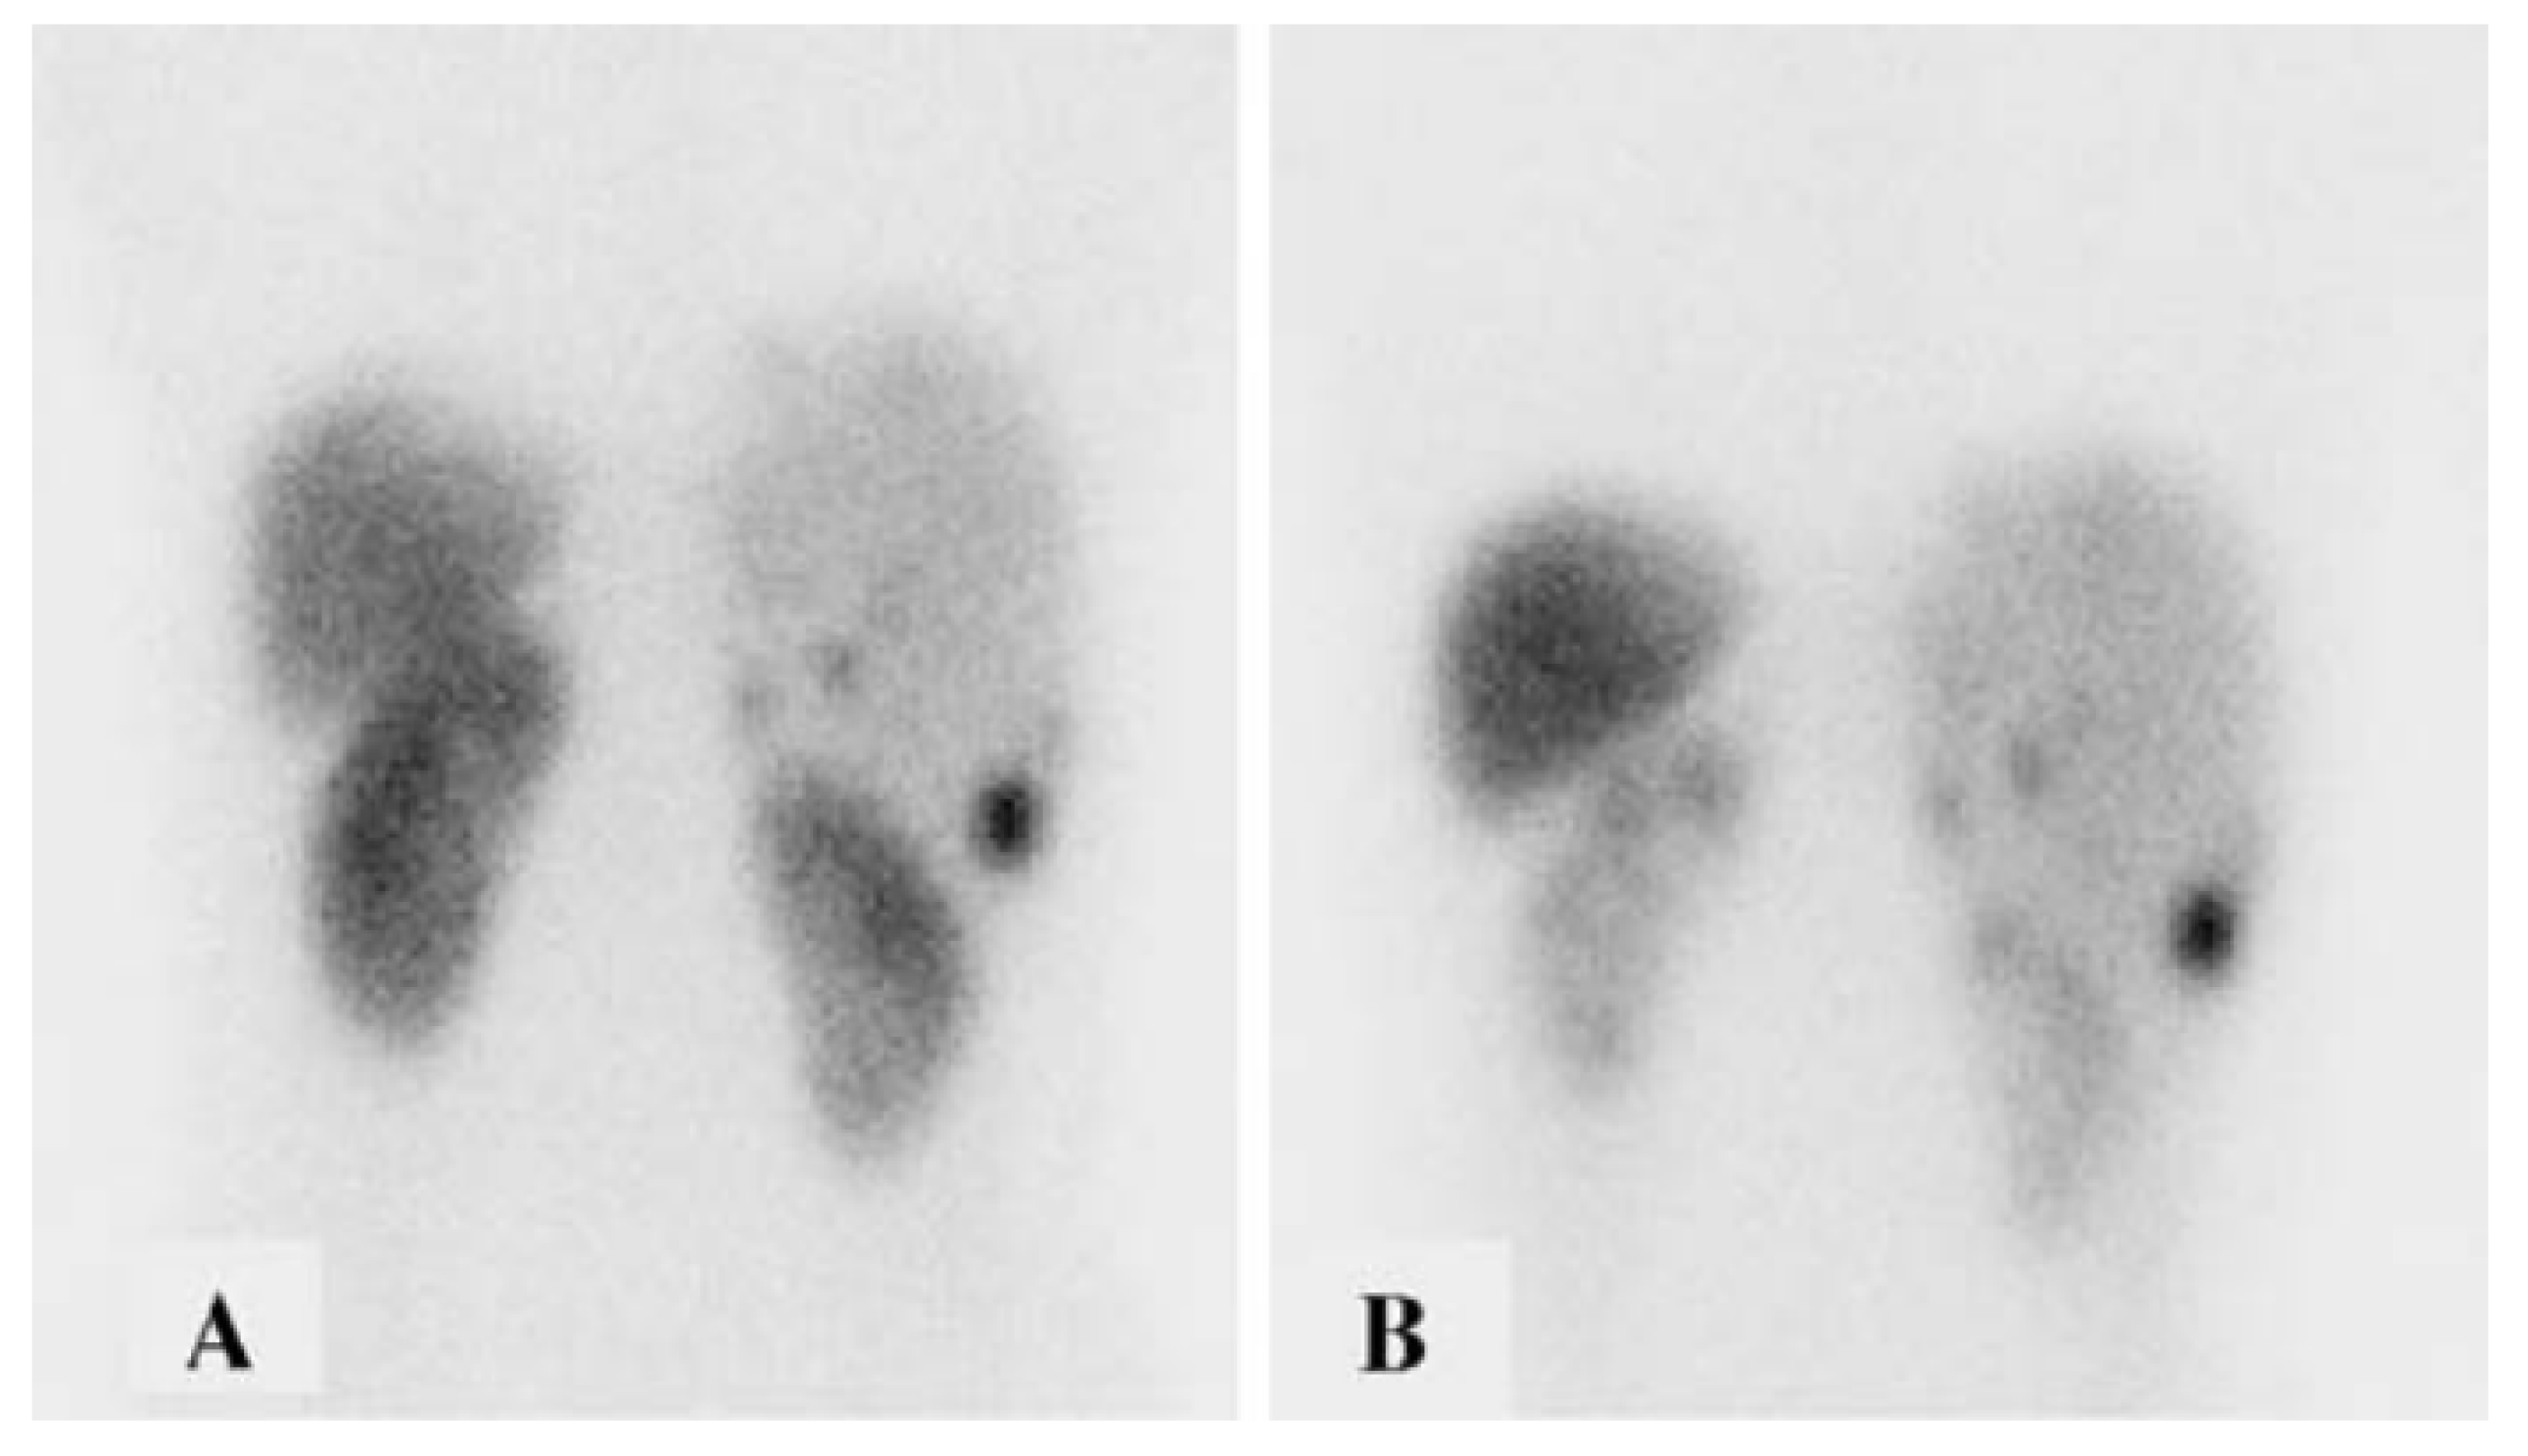

- Ilhan, H.; Wang, H.; Gildehaus, F.J.; Wängler, C.; Herrler, T.; Todica, A.; Schlichtiger, J.; Cumming, P.; Bartenstein, P.; Hacker, M.; et al. Nephroprotective Effects of Enalapril after [177Lu]-DOTATATE Therapy Using Serial Renal Scintigraphies in a Murine Model of Radiation-Induced Nephropathy. EJNMMI Res. 2016, 6, 64. [Google Scholar] [CrossRef] [PubMed][Green Version]